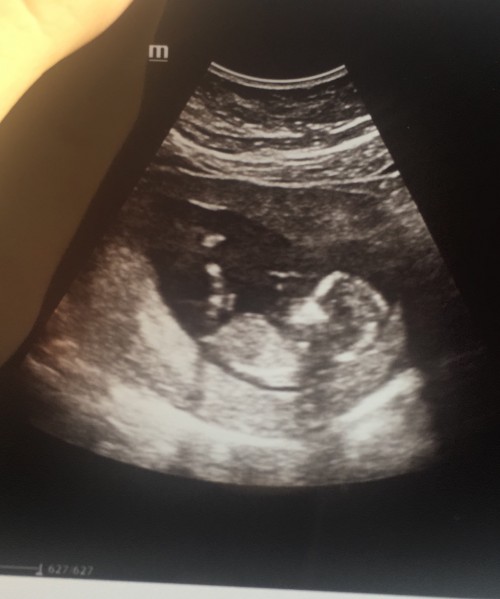

Kizlar bebeğinizin 11. Hafta ultrason görüntüsü elinde olan bana fotosunu atabilir mi nolur

Canım benımkıde şuan adet tarihine göre 14 haftalık falan olması gerekıyo ama 11 haftayla uyumlu belki senınki de öyledir, benımki raz değişik

image12 haftalıkken canım olursa? bi de bilgileri yazmıyo burda o haftadaki gelişim bilgilerini istersen yazabilirim. sorun ne hayırdır?

image

canım biraz geç oldu kusuruma bakma gündüz misafirim vardı cok telaşlıydım şimdi atabildim, sadece bunlar yazıyor baska bilgi yok